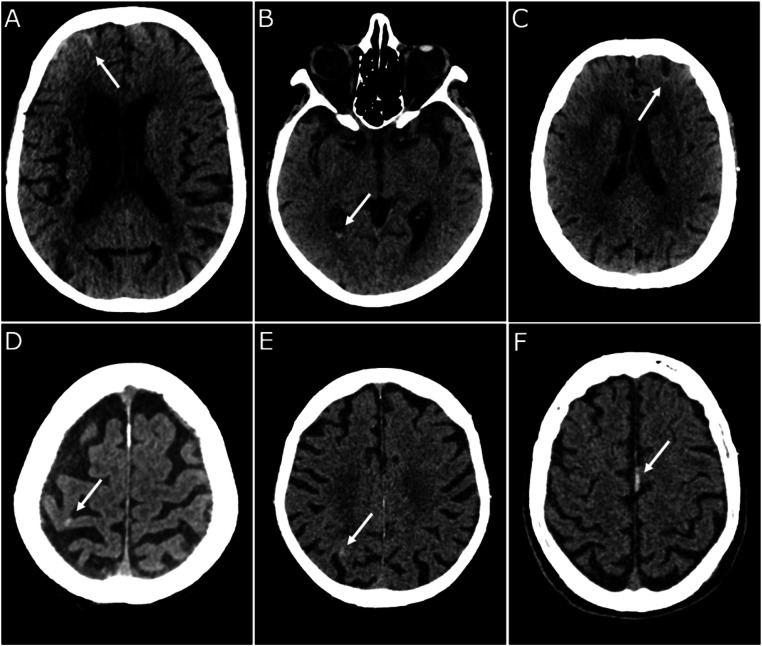

A total of 1415 patients were included. Post-traumatic intracranial hemorrhage (P < 0.001), brain herniation (P = 0.003), and fractures (P < 0.001) occurred statistically more frequently in the At-risk group. Six post-traumatic hemorrhagic brain injuries were found in the Not-at-risk group, that did not present any of the studied criteria, and all these injuries were minor (localized SAH; millimetric SDH). Furthermore, none of these required immediate or delayed surgical intervention, and no neurological deterioration or deaths occurred in these patients.

Abstract Image